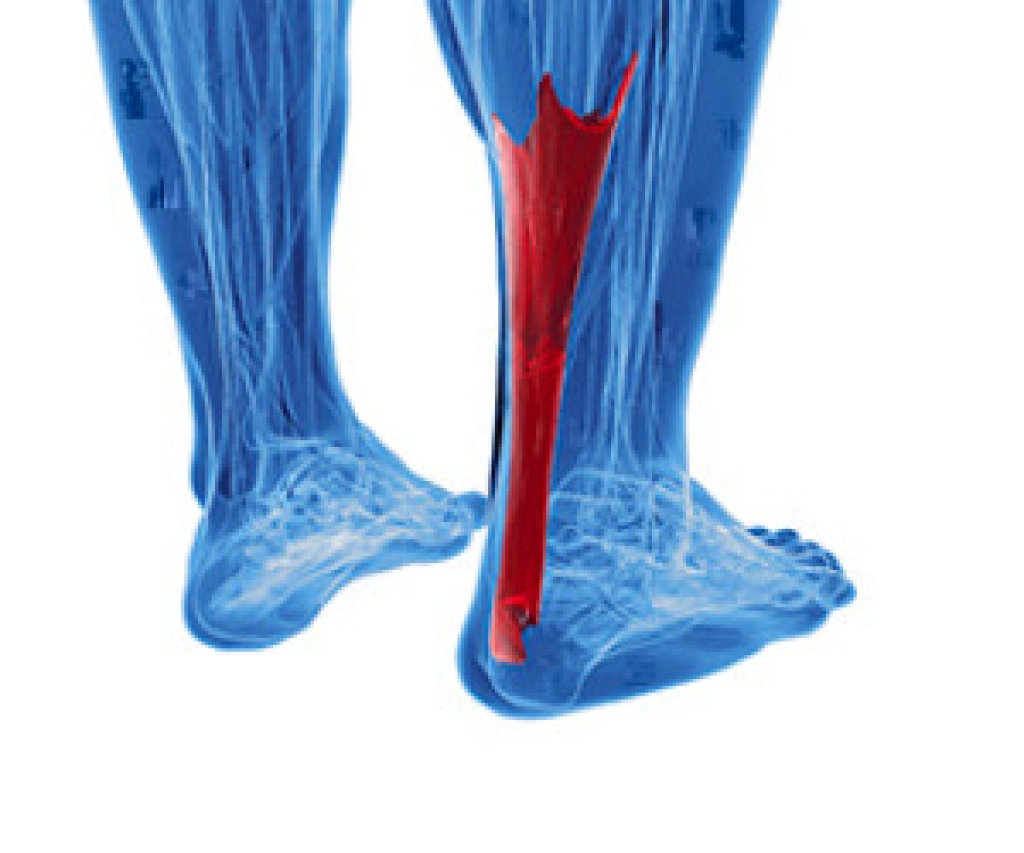

The Achilles tendon is considered to be the largest tendon in the body. Its function is to connect the heel to the calf muscles, and it is important for this tendon to maintain its flexibility and strength. It is typically put under pressure for the majority of the day as walking or running and jumping activities are completed. If an injury should occur to the Achilles tendon, it may become swollen and inflamed. This type of injury is known as tendonitis. A common symptom that can be associated with this condition may be pain in the heel and surrounding areas. If a rupture should occur, you may hear a popping sound emanating from the back of the heel. This is typically indicative of a serious injury, and medical attention should be sought as quickly as possible. If you have any pain in the back of the calf or in the heel, please consult with a podiatrist who can properly diagnose and treat an Achilles tendon injury.

The Achilles tendon is a tendon that connects the lower leg muscles and calf to the heel of the foot. It is the strongest tendon in the human body and is essential for making movement possible. Because this tendon is such an integral part of the body, any injuries to it can create immense difficulties and should immediately be presented to a doctor.

There are various types of injuries that can affect the Achilles tendon. The two most common injuries are Achilles tendinitis and ruptures of the tendon.